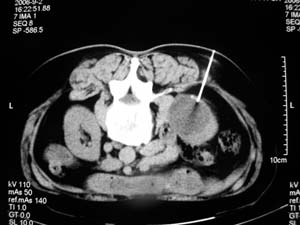

标题: DSA0075:[原创]肾囊肿穿刺硬化术 [打印本页]

标题: DSA0075:[原创]肾囊肿穿刺硬化术

不错,针好象应再深些。

穿的很准。

我们主要在ct引导下进行各种囊肿的穿刺引流,对于肾囊肿治疗的较多.穿刺成功后尽量抽尽囊液并且记录数量,抽尽后注入造影剂看看是否与尿路相通,然后用1/4的比例注入无水酒精进行硬化.跟踪观察治愈率达98%以上.